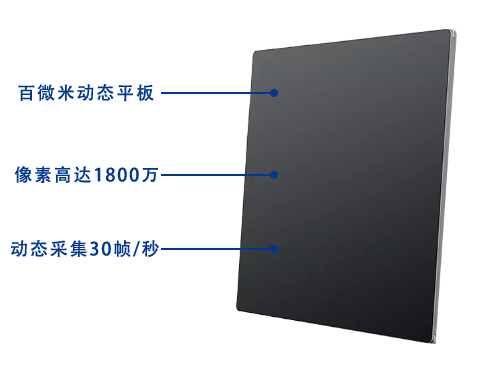

搭载17x17英寸动态平板探测器,动态帧率高达30帧/秒,突破传统盲拍局限,通过动态实时连续成像,对于重叠部位、易被遮挡的病灶进行多角度动态观察,瞬时实现高清点片,提升筛查诊断的精准性。